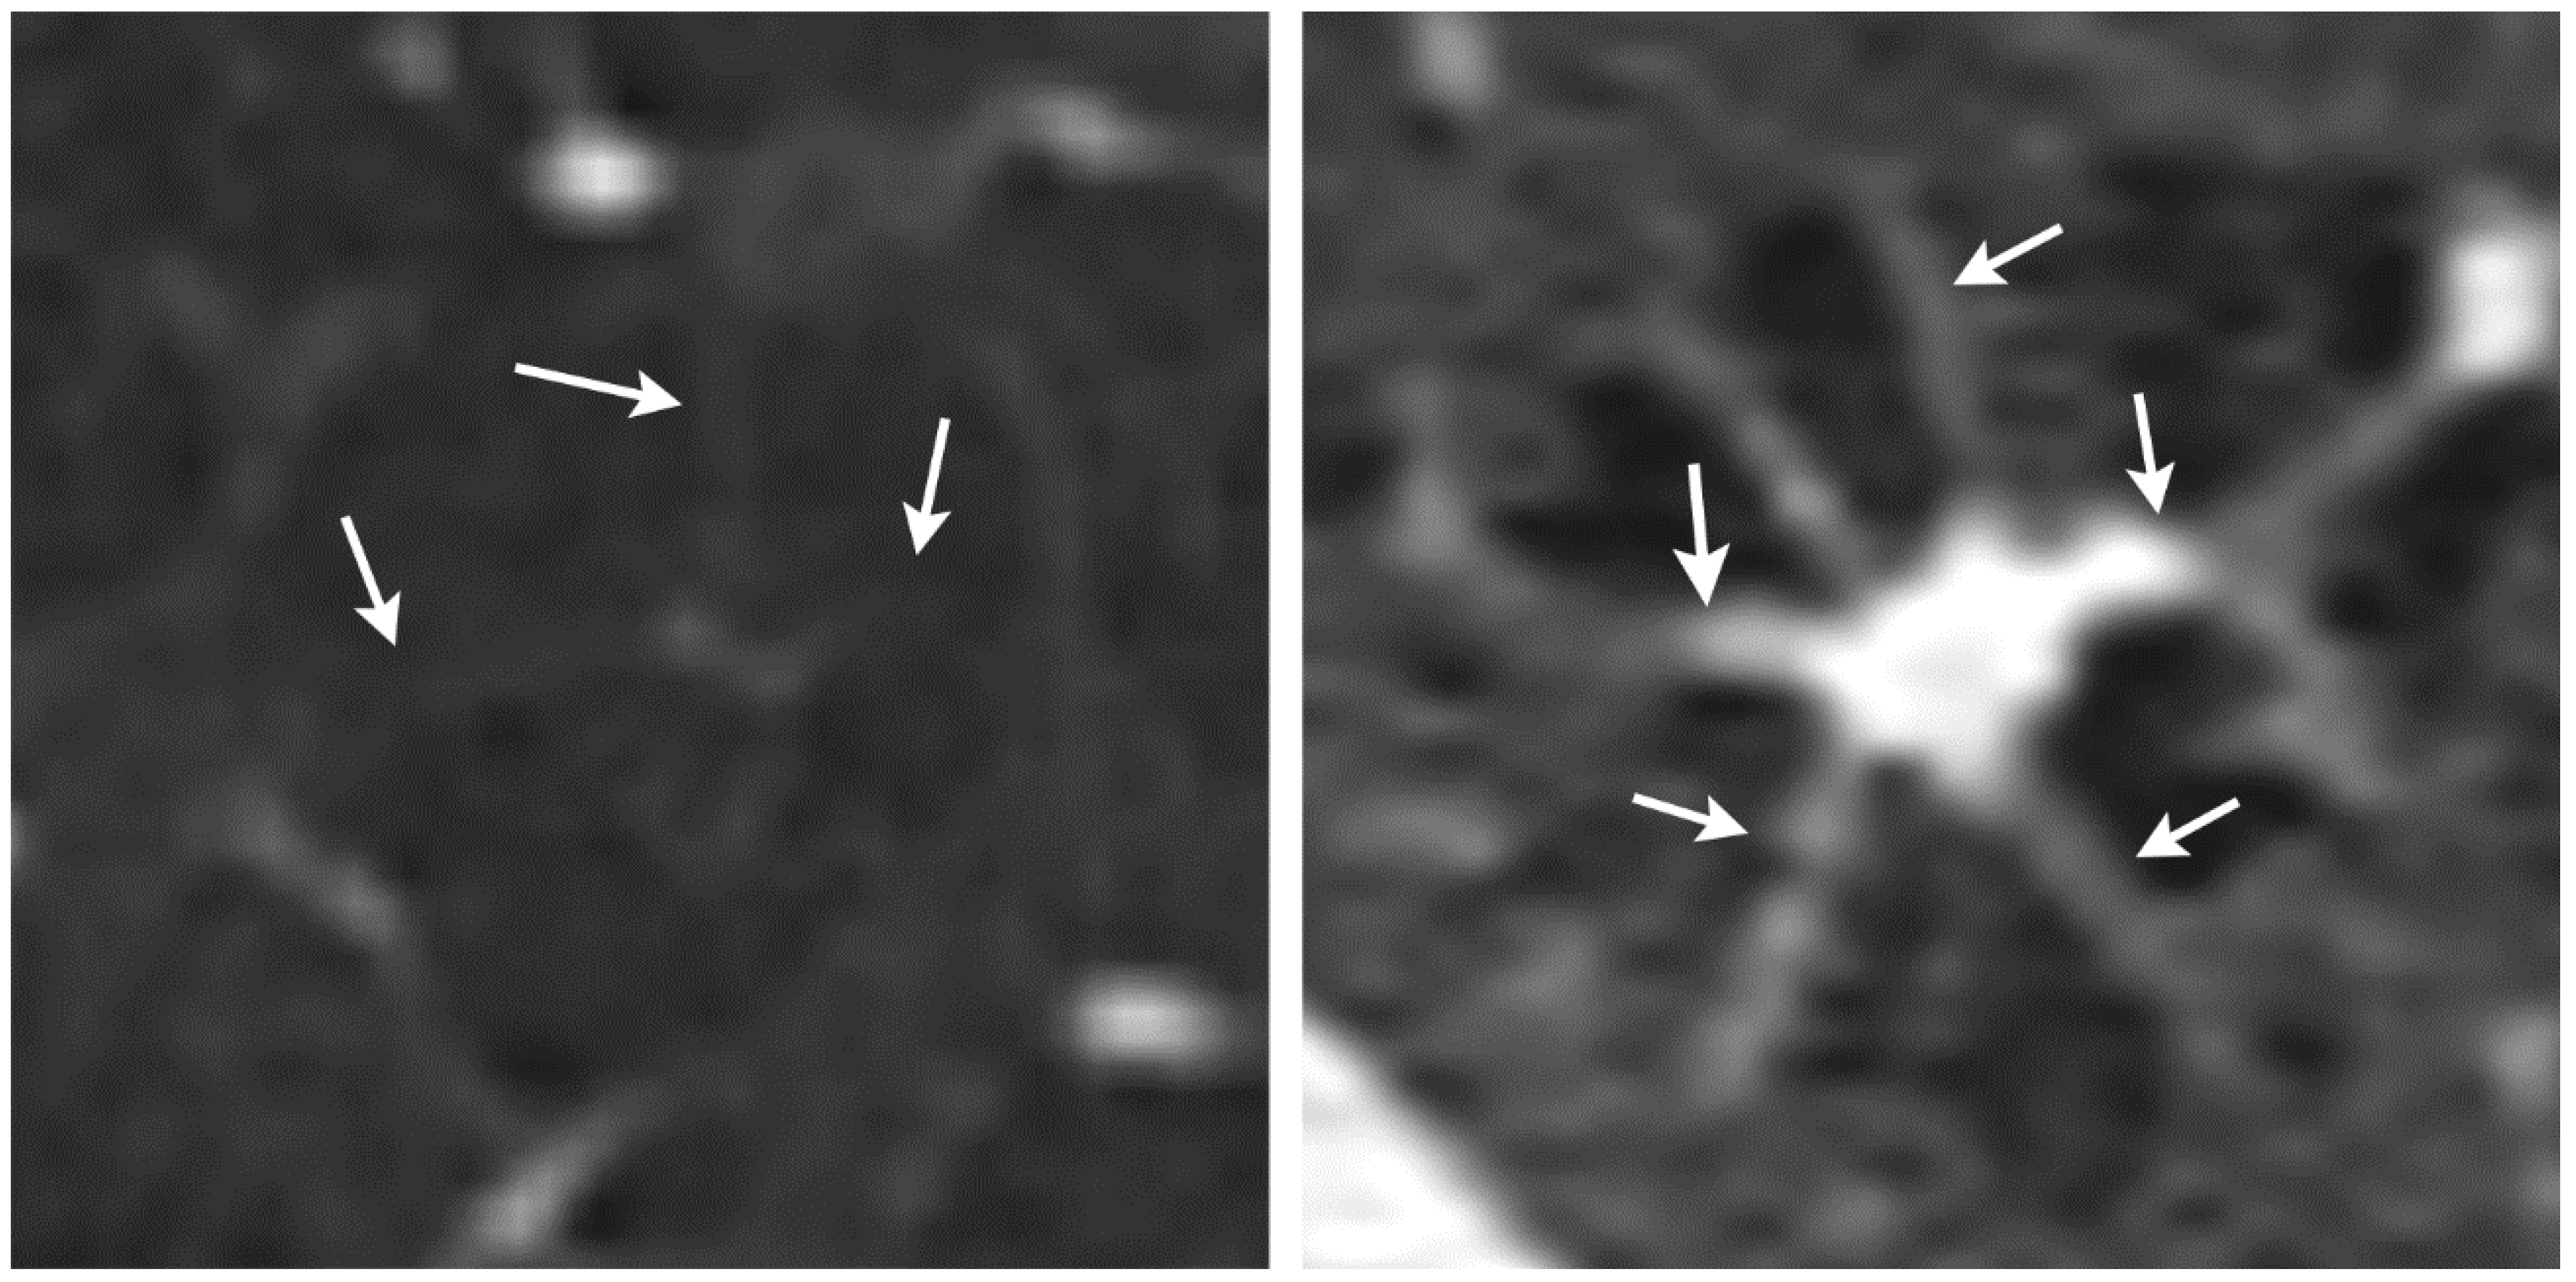

Although the combination of nodular and cystic lung disease and the bizarre form of the cysts for PLCH on HRCT are almost pathognomonic in some cases, the findings in other cases of PLCH are sometimes difficult to distinguish from other cystic lung diseases. One differential diagnosis to PLCH is centrilobular emphysema [14]. PLCH can form cystic lesions that resemble those seen in centrilobular emphysema. In addition, centrilobular emphysema may have a similar appearance to an octopus sign in that it often presents with some fine strands toward the centrilobular artery and bronchiole. We found that the octopus sign in PLCH has thicker strands toward the center, which forms the body of the octopus (Figure 3). Currently, we have only compared the octopus sign in PLCH with a few selected cases of centrilobular emphysema, and a diagnostic test study needs to be conducted to evaluate the discriminative performance of the octopus sign. Since both PLCH and centrilobular emphysema are smoking-related lung diseases, the octopus sign might contribute to the differentiation between centrilobular emphysema and PLCH. This differential diagnosis is of prognostic importance as PLCH can lead to fibrotic lung disease with unfavorable outcome [19].

Figure 3. Comparison between centrilobular emphysema (left) and Langerhans cell histiocytosis (right). The strands (arrows) pointing to the center of the lesion in centrilobular emphysema are thinner than those in PLCH.